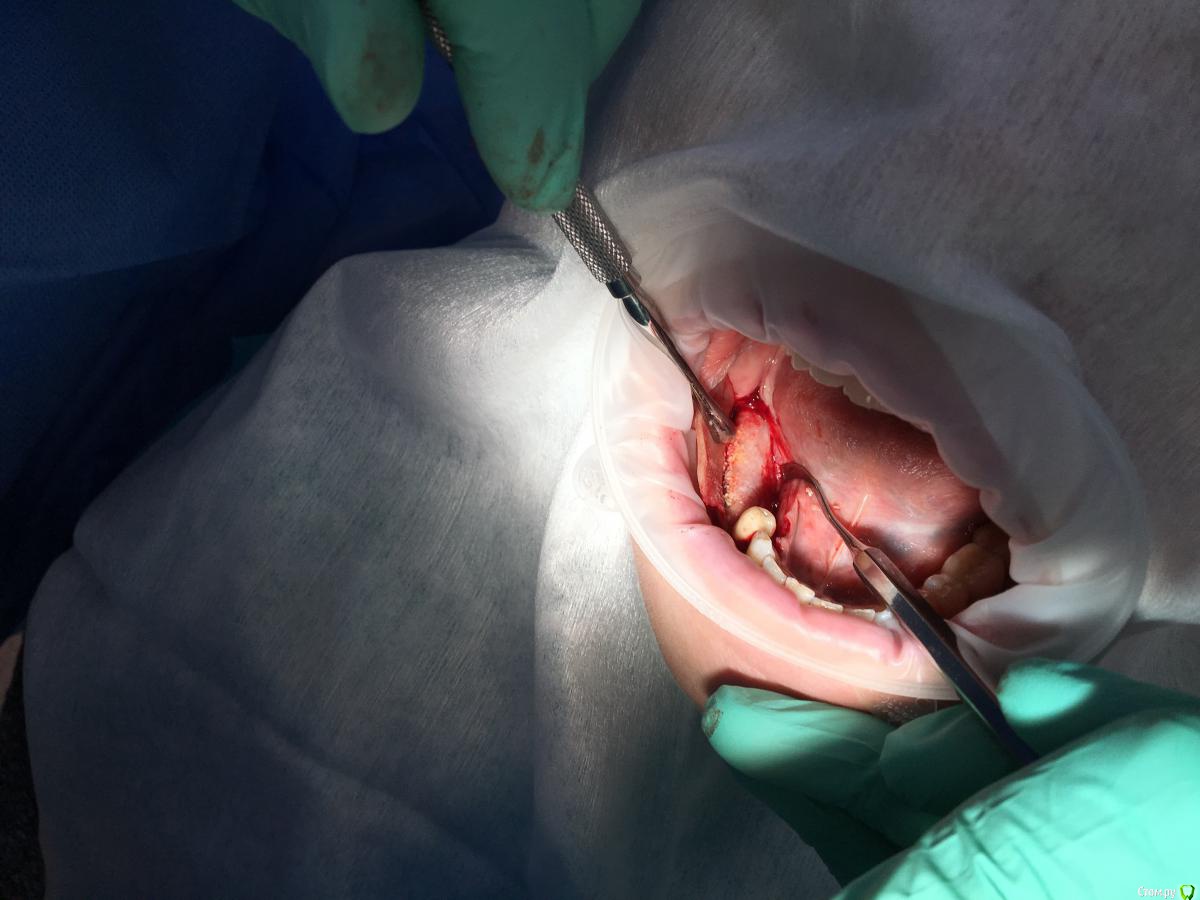

Shakirbura Опубликовано 8 ноября, 2017 Поделиться Опубликовано 8 ноября, 2017 Здравствуйте, коллеги!Раскрыл через 5 месяцев после нкр. Поверхностный слой материала легко соскреб распатором. Глубоко ковырять не стал. Был апатос микс + ауто 60/40. Почему такая картина, кто может подсказать?Есть надежда, что это станет костью? Ссылка на комментарий

kriokov Опубликовано 9 ноября, 2017 Поделиться Опубликовано 9 ноября, 2017 1 фотка в теме, это ламина на этапе раскрытия? Ссылка на комментарий

Shakirbura Опубликовано 10 ноября, 2017 Автор Поделиться Опубликовано 10 ноября, 2017 1 фотка в теме, это ламина на этапе раскрытия?Все верно. Ссылка на комментарий

kriokov Опубликовано 21 ноября, 2017 Поделиться Опубликовано 21 ноября, 2017 Все верно.У меня немного работ с ламиной (дороговато), из того что вижу1. ламина и через 6 мес полностью не деградирует, на раскрытии всегда ошметки были, у Вас время мало прошло, мембрана прям девственная, обычно она хоть частично интегрирована в мягкие ткани, хотя и легко отходит2. графт не созрел, сроки не выдержаны, но это не каша, так что думаю , раз болты встали, все ок будет3. еще думаю графта маловато, мембрана хорошо привинчена, а сняли, и под ней не густо4. На нижней челюсти Curved я бы не стал при концевом дефекте использовать, но это имхо 3 Ссылка на комментарий